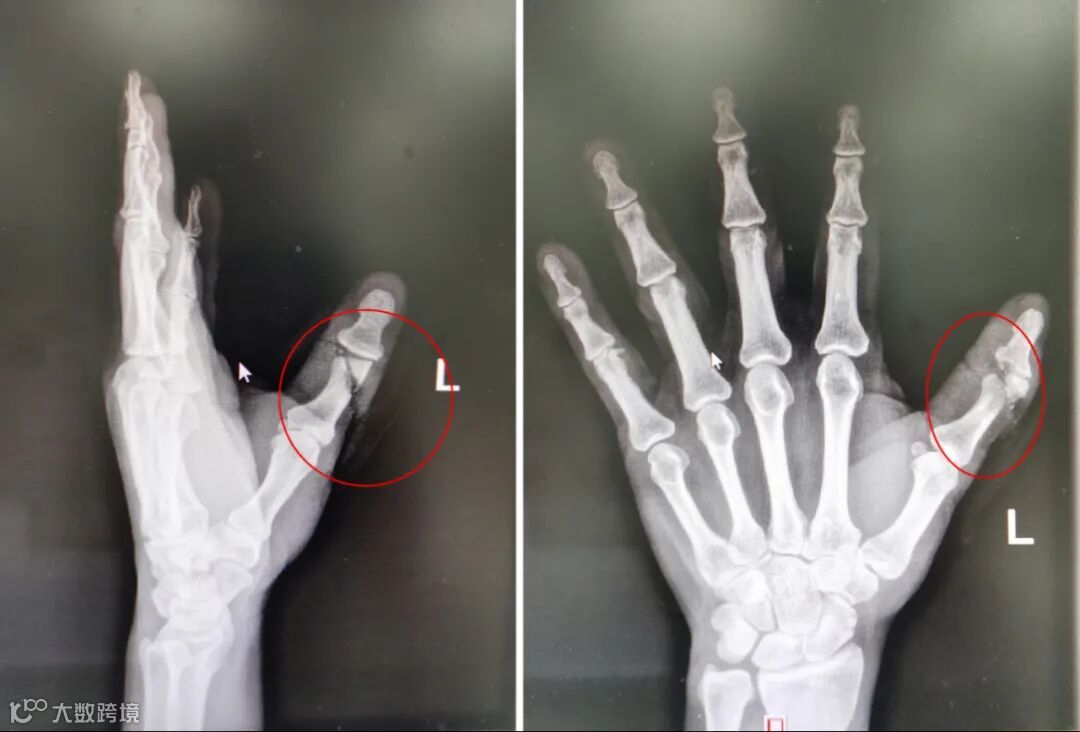

据了解,温师傅是前几天才出院的患者,1月15日18时,在北海务工的48岁的钦州人温师傅在工作时左手拇指不慎被电锯锯伤,到市人民医院急诊科就诊,急诊拍片显示左手第1指近节指骨远端骨折,周围软组织损伤。

完善CT检查后,覃育接主治医师发现受伤的问题非常的严重:温师傅左手拇指不完全离断伤、左手拇指近节指骨开放性指骨骨折、左手拇指伸指肌腱断裂、左手拇指屈指肌腱断裂,左手拇指背侧有一条约4cm长的锯齿状伤口,关节面完全性骨折,伸指肌腱、屈指肌腱完全断裂,尺、桡侧固有神经、固有动脉均完全断裂,左手大鱼际部还有一约3.5cm斜形挫裂伤口,深达大鱼际肌。